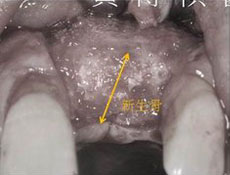

因為長期缺牙,齒槽骨僅剩0.2mm,使用人工骨粉進行補骨手術後,可見長出了厚厚的新生骨, 足以支撐植入的人工牙根。 |